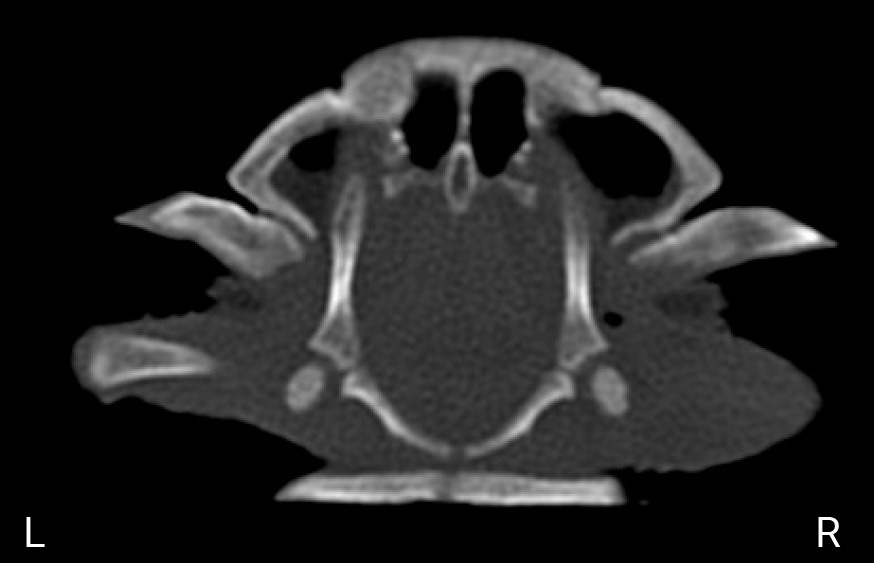

Спустя 12 часов после хирургического вмешательства животному была повторно выполнена процедура компьютерной томографии. Послеоперационная КТ показала нормальное анатомическое расположение головки бедренной кости относительно вертлужной впадины (фото 10, 11). Ограничение подвижности прооперированной конечности не проводилось. Спустя 24 часа черепаха была выписана домой.